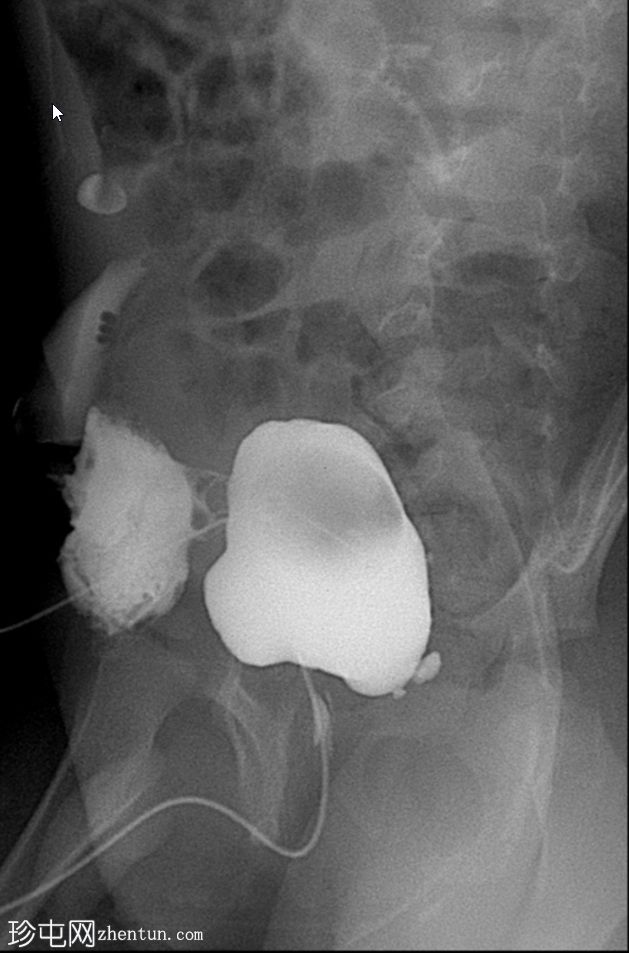

显示膀胱输尿管反流(VUR)

斜位片

使用纱布进行外部压迫成功阻塞了脐尿管开口,膀胱充盈良好。左侧输尿管和肾盂肾盏系统可见膀胱输尿管反流,符合II/III级VUR。输尿管轮廓正常,无憩室,无管壁增厚。尿道显影正常,未见后尿道瓣膜或狭窄。无肾积水。

首次尝试使用Foley球囊阻塞脐尿管开口效果不佳。纱布阻塞法可提供更完整的密封,使造影剂得以充分滞留并充盈膀胱。这使得排尿期能够显示II/III级膀胱输尿管反流。